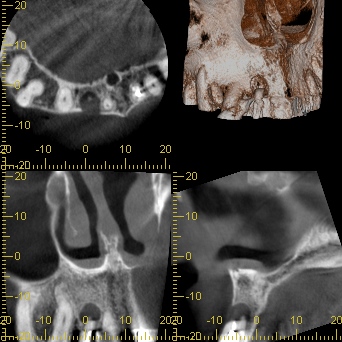

初診時レントゲン、CT

膿がおおきい

「前歯の違和感」という主訴に対して、まずは客観的な評価が必要です。今回、以下の検査を実施しました:

- デンタルレントゲン撮影

- CT撮影

検査の結果、インプラント周囲の骨の状態、インプラント体の位置、周囲組織の状態など、すべてにおいて問題は認められませんでした。これは、8年間適切にメインテナンスを継続してきた成果と言えるでしょう。